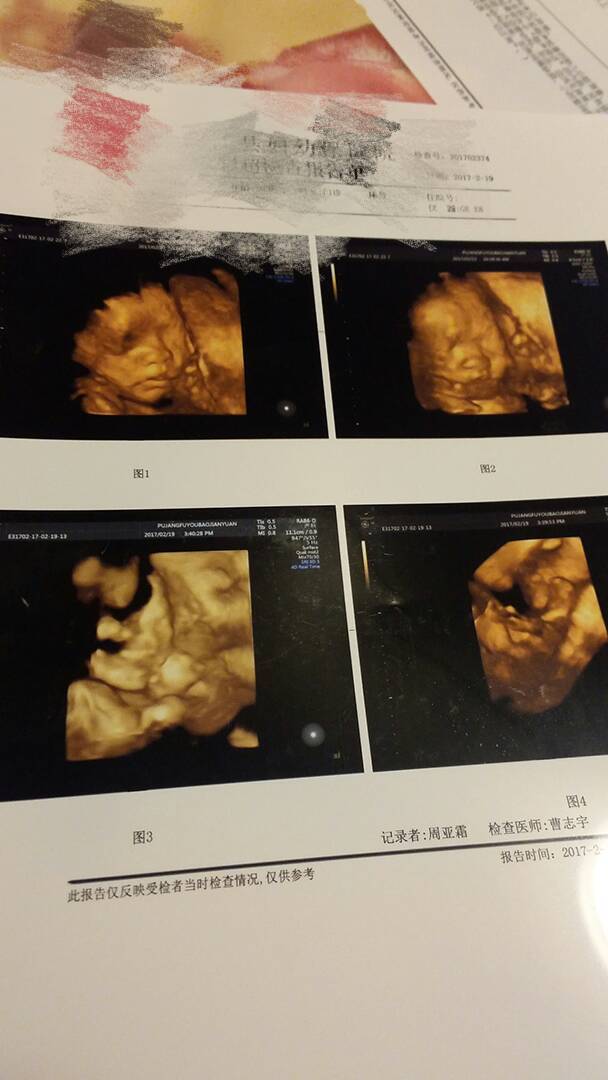

四维终于做好了,宝宝好像我哈哈

四维做了四次,前几次看不见脸,耳朵,和心脏,医生姿势摆得不好,蜷着和虾米似的,最后一次,医生说没大问题,我就说不复查了,就让他把单子打出来了。医生挺负责的,叮嘱我下次彩超时候看下宝宝的耳朵,这次就只看见一只耳朵,另外一只被胎盘挡了